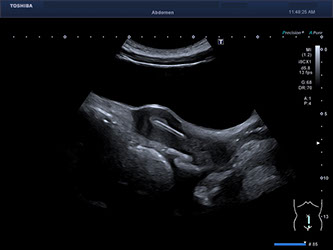

Ultraschall

- Weibliches Becken (transabdominell, transvaginal)

- Nierenultraschall zum Ausschluss Harnstau